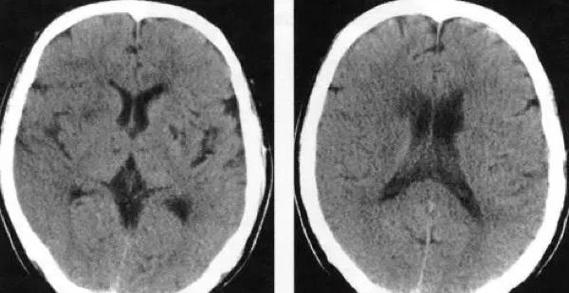

(图片来源网络,侵删)- 正常脑组织和缺血早期脑组织的密度非常接近,CT无法区分。

- 只有当缺血持续足够长时间(通常超过6小时),脑细胞开始死亡,血管结构也发生破坏,导致血管源性水肿(细胞间隙液体增多),这时脑组织才会出现明显的密度变化,在CT上表现为低密度灶。